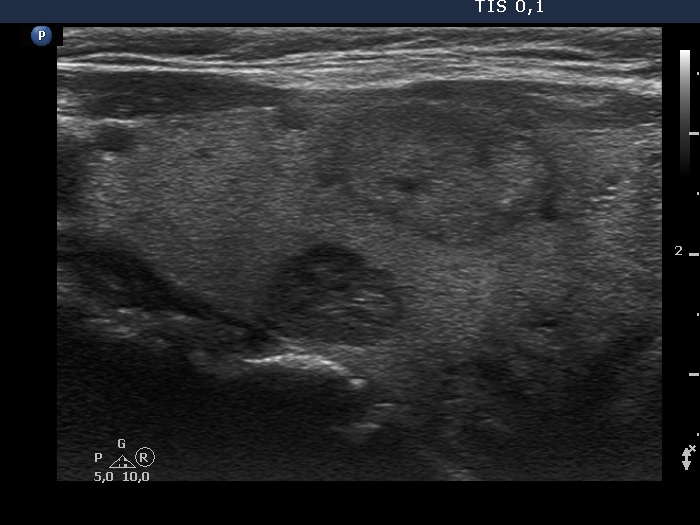

Ultrasonography. The thyroid was echonormal and contained several nodules of different echogenicities including a hypoechogenic one in the dorsal part of the left lobe and a minimally hypoechogenic lesion presenting groups of echogenic foci in the ventral part of the left lobe.

A single bright echogenic focus within the right nodule can be seen in the video. This figure belongs to punctate echogenic foci subgroup.